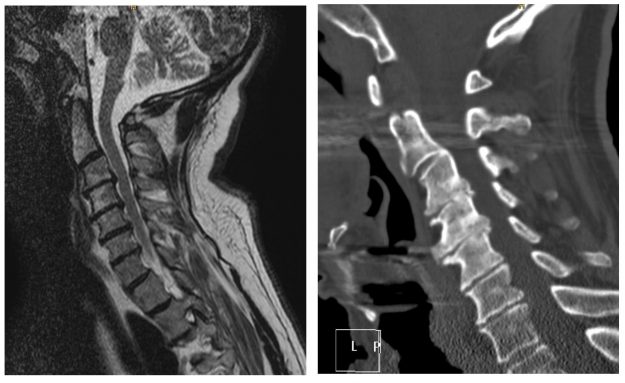

Ασθενής άδρας 33 ετών με έντονη οσφυαλγία απο 12μήνου και επιδείνωση από διμήνου. Ο απεικονιστικός έλεγχος ανέδειξε σπονδυλολίσθηση 2ου βαθμού σε έδαφος σπονδυλόλυσης στο ύψος Ο5-Ι1. Διενεργήθη διαδερμική (ελάχιστα επεμβατική) σπονδυλοδεσία στο επίπεδο Ο5-Ι1 Ο ασθενής παρουσίασε σημαντική βελτίωση της συμπτωματολογίας του. Εξήλθε του νοσοκομείου την 3η μετεγχειρητική ημέρα. Προεγχειρητική Αξονική Τομογραφία Μετεγχειρητική Αξονική Τομογραφία…